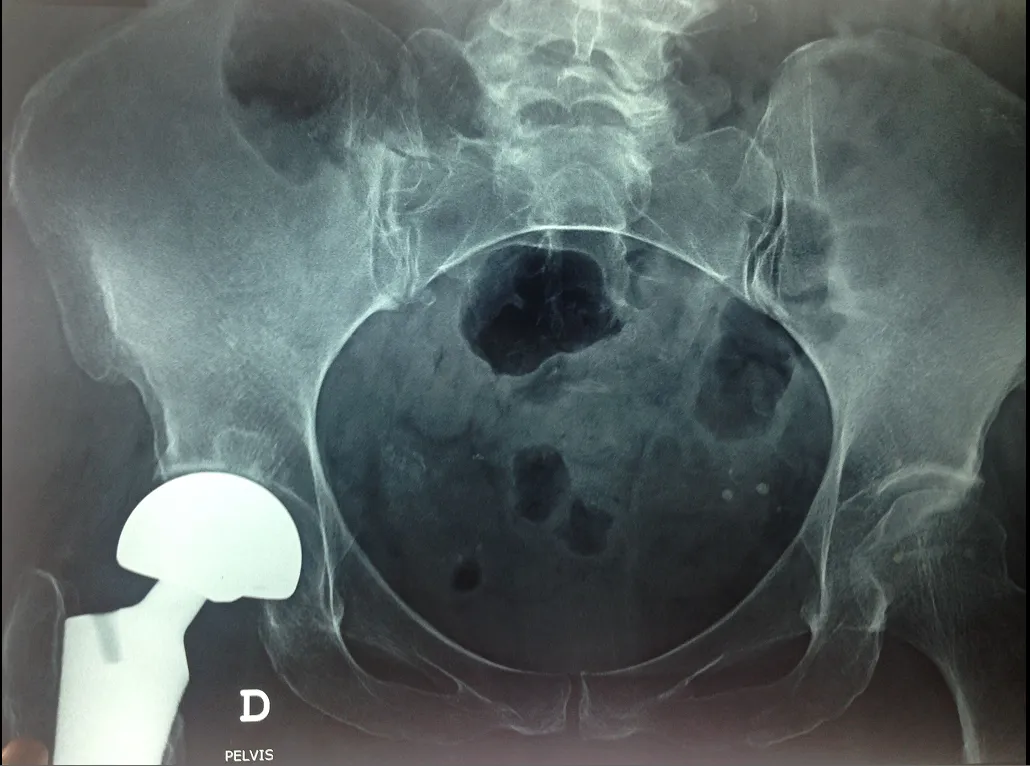

Dislocation of the hip prosthesis

We are talking about a dislocation of the hip prosthesis when the artificial femoral head comes out of the prosthetic acetabulum. Functional disability, pain and shortening of the lower limb are the main manifestations of dislocation of the prosthetic femoral head.

Radiological diagnosis is obvious most of the time and easy to detect.